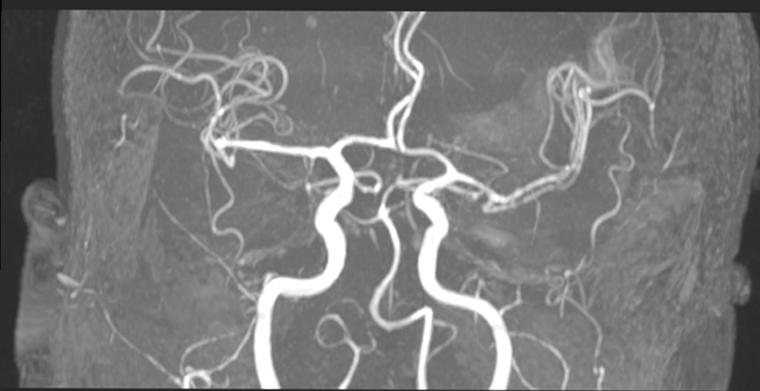

Anjiyo Sonrası Kolda Morarma Neden Olur ve Ne Yapılmalıdır?Anjiyografi, damarsal yapıların incelenmesi amacıyla gerçekleştirilen bir görüntüleme yöntemidir. Bu işlem sonrasında kolda morarma, çeşitli nedenlerden kaynaklanabilmektedir. Morarma, genellikle kan damarlarının hasar görmesi ve kanın çevre dokulara sızması sonucu meydana gelir. Bu makalede, anjiyo sonrası kolda morarmanın nedenleri, belirtileri ve bu durumda yapılması gerekenler ele alınacaktır. Anjiyo İşlemi ve Morarma MekanizmasıAnjiyo işlemi, genellikle kol veya bacak gibi periferik damarlara kateter yerleştirilerek gerçekleştirilir. Bu işlem sırasında, damar duvarında yaralanma meydana gelebilir. Bu yaralanmaların sonucunda kan, damar dışına sızarak çevre dokularda birikir. Morarma, bu birikim nedeniyle oluşur ve genellikle aşağıdaki nedenlerle ilişkilidir: